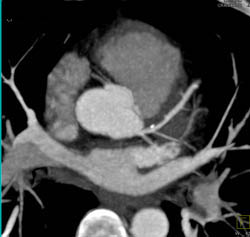

Plaque in LAD